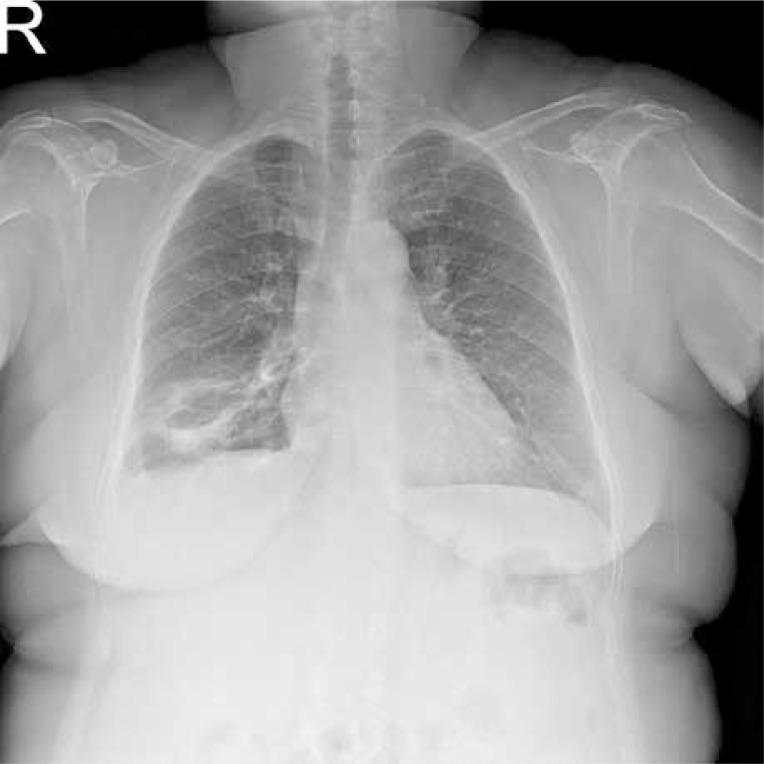

多发性肺类风湿结节。

Multiple pulmonary rheumatoid nodules.

We present a case of 45-year-old female patient with the diagnosis of seropositive rheumatoid arthritis, who was admitted to our rheumatology department with exacerbation of the disease. The patient's disease activity score (DAS 28) was 6.9. Physical examination revealed changes in the lung auscultation as a rough breathing sound at the middle and lower lobe of the right lung. Chest X-ray revealed multiple nodular densities in both lungs. Lung biopsy was performed for the diagnosis and revealed necrotizing granulomas with central fibrinoid necrosis surrounded by epithelioid cells. Such a histopathological picture is typical for rheumatoid nodules. Finally the patient was treated with rituximab, with significant improvement.

我们报告一例45岁血清阳性类风湿关节炎女性患者,因病情加重入住我院风湿科。患者的疾病活动评分(DAS 28)为6.9。体格检查发现肺部听诊有变化,右肺中、下叶呼吸音粗糙。胸部X线显示双肺多发结节状密度影。为明确诊断进行了肺活检,结果显示坏死性肉芽肿,中央为纤维蛋白样坏死,周围是上皮样细胞。这种组织病理学表现是类风湿结节的典型表现。最后患者接受了利妥昔单抗治疗,病情显著改善。